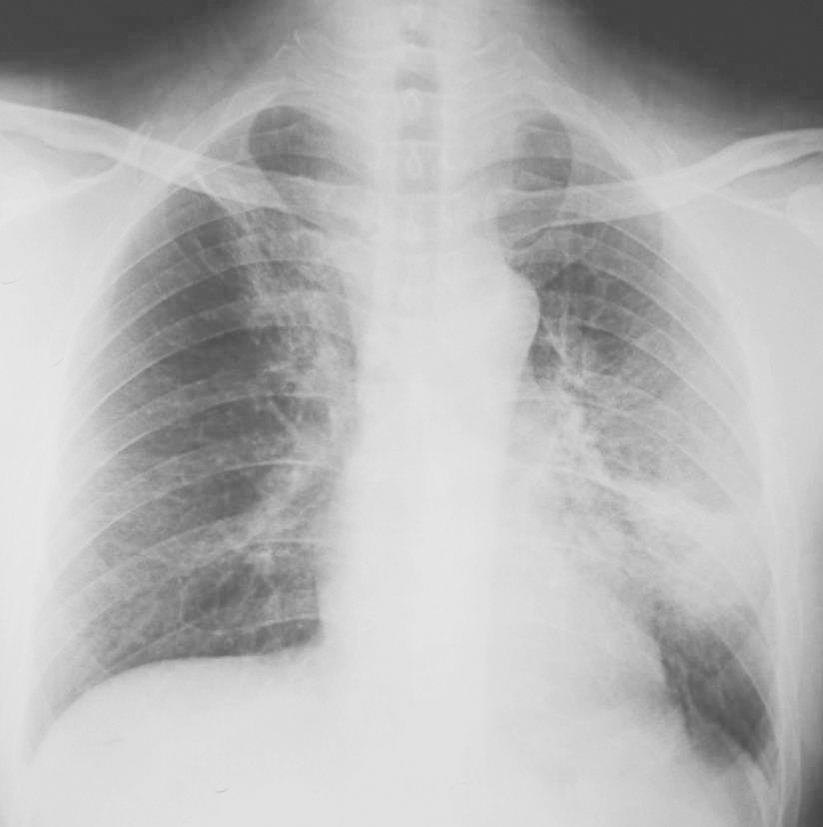

图1|X线胸片(2009-11-04)

X线胸片示左下叶斑片影,右上肺纹理增多